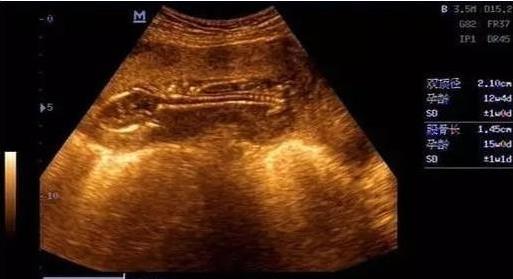

8.看B超单

男孩子在怀孕两个月前是长型的,女孩子是椭圆或是圆型。从B超单上看形状,像茄子或长条状的是男宝宝可能性大,圆圆的是女宝宝可能性大;看数据,如果长和宽的相差在一倍以上男宝宝可能性大。长和宽相等女宝宝可能性大;B超显示宝宝脸朝外的怀男孩,面对妈妈的怀女孩。